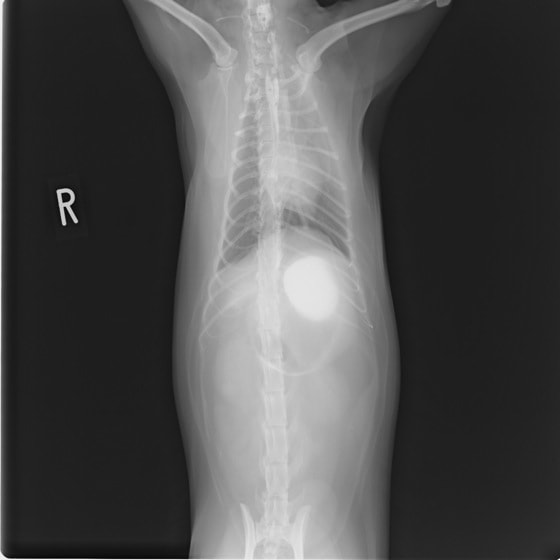

11歳 ミニチュア・ダックス 去勢オス

主訴:焼き鳥の竹串を食べたとの事で来院しました。元気・食欲は問題なく、嘔吐などの症状もありませんでした。便にも竹串が1/3程でているとの事でしたが、全ての竹串が出ていないため、内視鏡検査を実施致しました。

内視鏡検査所見:胃内に竹串の先端部分が残っていたため、異物鉗子にて摘出しました。胃内は、全体的に炎症を伴い、出血している部位も確認されました。摘出後は、胃粘膜保護薬・プロトンプインヒビター(胃薬)の内服2剤ならびに食事療法により経過は良好です。

摘出した竹串

内視鏡下写真

◎竹串誤飲は、異物の1位と言われるほど多く認められています。竹串は、先端が尖っているため消化管穿孔などを起こし、命に関わることもあります。万が一、ご自宅や散歩中に串などを食べてしまった場合は、病院まですぐご連絡下さい。また竹串は、食道を傷つけ・穴をあける恐れなどもあるため無理に吐かせる事は絶対にしないで下さい。本症例は、内視鏡下にて摘出が可能でしたが、状況によっては開腹が必要となる場合もあります。